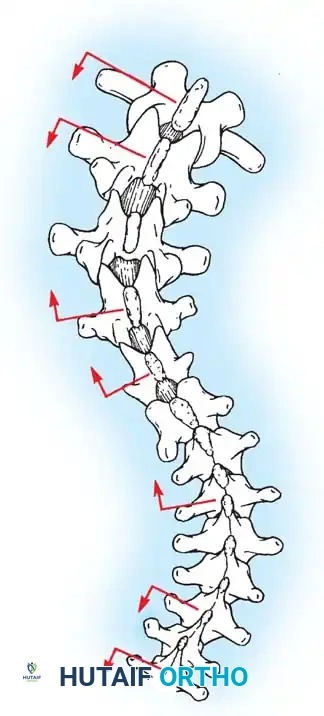

Biomechanics of Bone Grafting

Bone graft incorporates most effectively under compressive loads and is biologically disadvantaged in environments of distraction. Therefore, in scoliosis correction, if autogenous bone is limited, it should be preferentially concentrated on the concave side of the curve, which is subjected to compressive forces, rather than the convex side, which experiences tension. Furthermore, the farther the fusion mass is placed from the instantaneous axis of rotation, the more effectively it will neutralize movement across that axis.